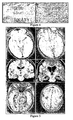

- FIG. 5 Brain magnetic resonance imaging (MRI) findings in three patients.

- A, B MRI of Patient I at symptom presentation (A) and after partial clinical improvement and cerebrospinal fluid normalization with immunotherapy (B); note that the clinical and MRI improvement started to occur before tumor resection.

- C, D MRI of Patient 2 at symptom presentation (C) and 4 months later (D); this patient developed rapidly progressive neurological deterioration that did not respond to immunotherapy.

- the autopsy demonstrated that the ovarian cyst was a mature teratoma of the ovary.

- E, F MRI of Patient 3 at symptom presentation; note the mild fluid-attenuated inversion recovery hyperintensity in medial temporal lobes and right frontal cortex. After immunotherapy and tumor resection, the MRI was normal (not shown).

Figure 5 : Brain magnetic resonance imaging (MRI) findings in three patients. (A, B) MRI of Patient I at symptom presentation (A) and after partial clinical improvement and cerebrospinal fluid normalization with immunotherapy (B); note that the clinical and MRI improvement started to occur before tumor resection. (C, D) MRI of Patient 2 at symptom presentation (C) and 4 months later (D); this patient developed rapidly progressive neurological deterioration that did not respond to immunotherapy. The autopsy demonstrated that the ovarian cyst was a mature teratoma of the ovary. (E, F) MRI ofPatient 3 at symptom presentation; note the mild fluid-attenuated inversion recovery hyperintensity in medial temporal lobes and right frontal cortex. After immunotherapy and tumor resection, the MRI was normal (not shown). -